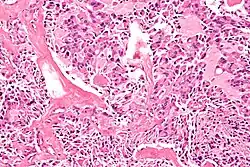

Micrograph of a medullary thyroid carcinoma, as may be seen in MEN 2A and MEN 2B. H&E stain